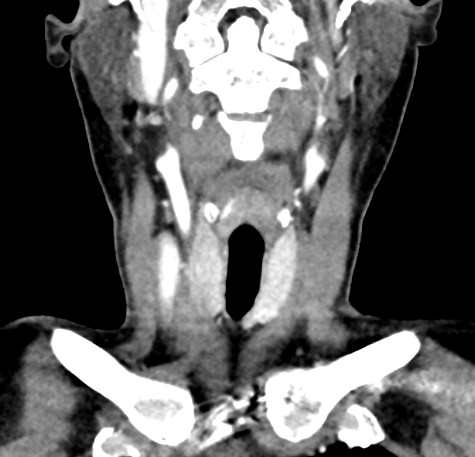

Мультиспиральная компьютерная томография – это высокоинформативный лучевой метод диагностики различной патологии мягких тканей шеи, включая воспалительные заболевания, травматические повреждения и опухолевые процессы. КТ позволяет оценить состояние щитовидной железы, паращитовидных желез, гортани, верхней части пищевода, магистральных сосудов шеи, шейных лимфоузлов и окружающих мягких тканей.

Метод КТ основан на применении рентгеновского излучения. Однако в отличие от обычного рентгена, при котором снимки производятся в одной плоскости, при КТ излучатель рентгеновских лучей постоянно двигается вокруг объекта исследования, проводя сканирование в различных плоскостях, а затем трансформируя полученные данные в цифровые трехмерные изображения. Это дает возможность визуализировать органы и ткани в мельчайших подробностях, а с помощью объемных 3D-реконструкций наглядно оценить пространственное расположение органов и патологических образований.

Рентгеновские лучи лучше всего поглощаются плотными структурами, такими как костная ткань. Поэтому кости хорошо видны на снимках КТ. Это делает компьютерную томографию незаменимой при необходимости обследования, в частности, костного скелета гортани. Однако для улучшения визуализации мягких тканей требуется введение специального контрастного препарата, поэтому КТ мягких тканей шеи проводится с контрастным усилением.

Для контрастирования используется йодсодержащее контрастное вещество, которое в составе рентгеноконтрастного препарата вводится в вену пациенту непосредственно во время исследования. Благодаря способности контраста поглощать рентгеновские лучи на снимках КТ хорошо контрастируются кровеносные сосуды и опухолевые образования, имеющие, как правило, развитую сосудистую сеть. Методика внутривенного болюсного контрастирования помогает обнаружить воспалительные изменения, отличить доброкачественные опухоли от злокачественных, выявить поражение лимфатических узлов и степень прорастания опухоли в магистральные сосуды и окружающие ткани.